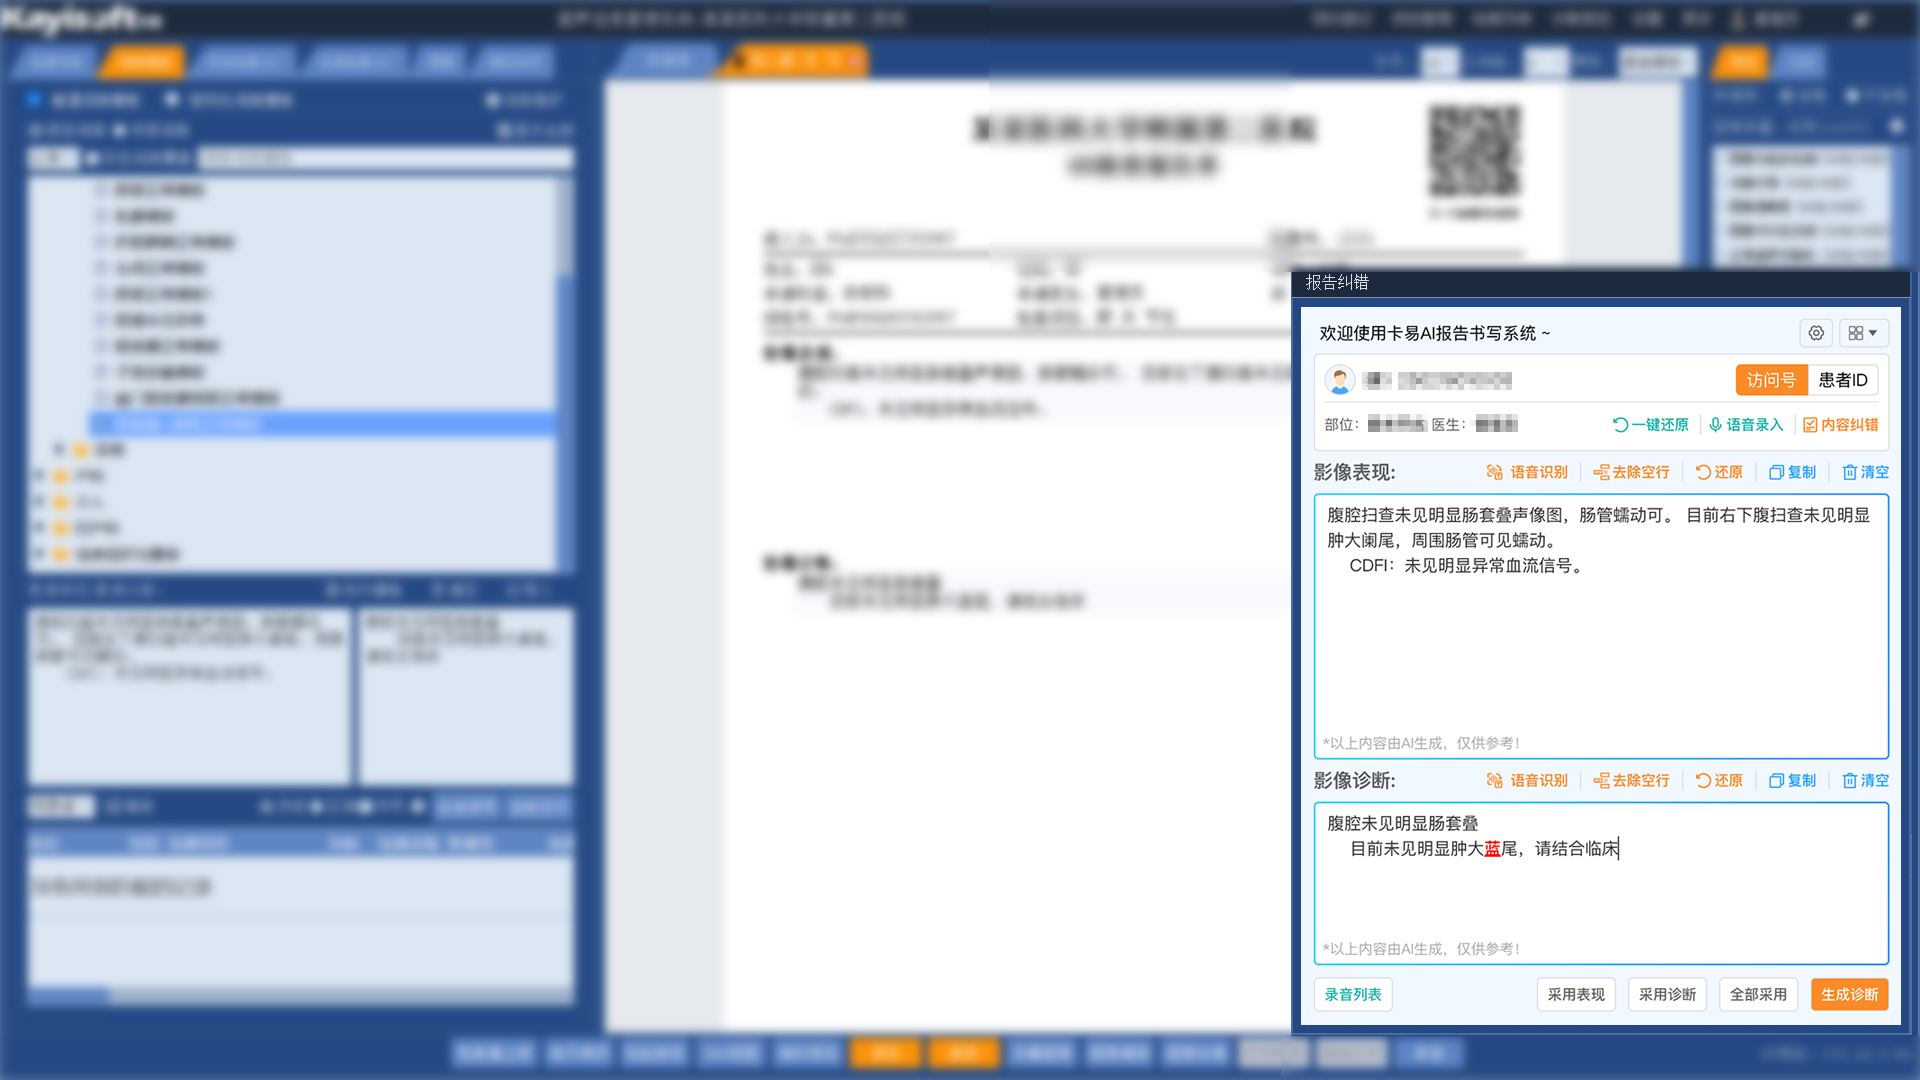

基于AI影像辅助诊断结果,影像云可自动生成结构规范、内容准确的影像检查报告。这不仅有助于医疗机构规范报告管理,还能显著提升医生撰写和审核报告的效率。

基于海量医学数据和影像特征,可以提供诊断建议和相似病例参考,可以整合患者的影像、病理等多模态数据,进行综合分析,为医生提供更全面、精准的诊断依据。可以自动比对患者治疗前后的影像,例如化疗前后的肿瘤大小变化、放疗前后的病灶密度变化等,量化病灶变化,辅助医生评估治疗效果。